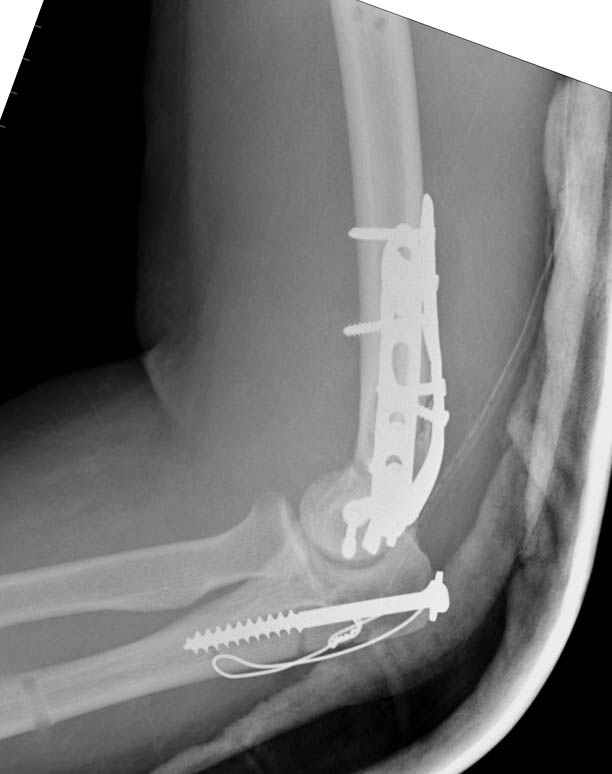

Примерный случай, только перелом был открытый, в задне-медиальной стороне рана около 2 см по характеру "изнутри кнаружи", неврологический статус со слабостью сгибания мизинца, также слабая абдукция и аддукция указательного пальца и сгибания в кисти.

Больному сделали обработку и наложили временный аппарат внешной фиксации плечо-предплечье.

На шестой день сделали открытую репозицию чрезлоктевым доступом двумя locking plate, локтевой нерв был ушибленным, после операции положительная динамика в Flexor Carpi Ulnaris. Фиксацию локтевого отростка произвели tension band technique с дополнительным шурупом.

Этапы операции на снимках....